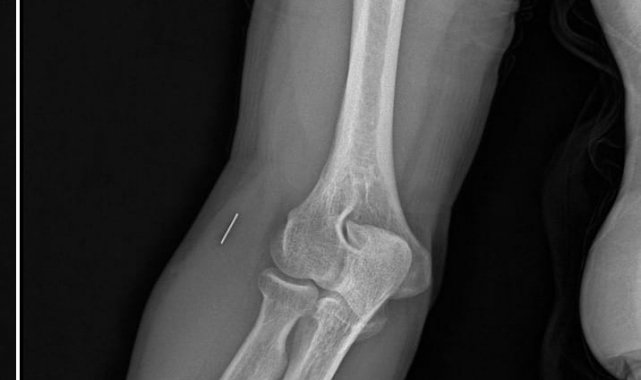

Öte yandan, ameliyatların ardından ağrıları devam eden Güleryüz'ün kolunda metal parça bulunduğu ve bu parçanın parmak bölgesinden dirseğe doğru ilerlediği öne sürüldü. Ayrıca, fabrikada temizlik personeli olarak çalışan Nurettin Güleryüz'ün hastane sürecinde işten çıkarıldığı da öğrenildi.

"Doktorlara bileğime doğru ağrılarım olduğunu sürekli ifade etmeme rağmen beni dinlemediler. Sonradan kolumda metal kaldığını öğrendik. Bunun ihmal olduğunu düşünüyoruz. Çünkü kola metal nasıl girebilir? Ben 9 aydır çalışamıyorum. Kalp rahatsızlığım sebebiyle yüzde 46 engelliyken şu anda yüzde 75 engelli durumuna düştüm. Erken emeklilik dilekçesi verdim ancak henüz sonuç gelmedi. Bu konuda çok mağdurum. Yetkililerin bunu duymasını istiyorum. Savcılığa suç duyurusunda bulunduk. Yaklaşık 9 aydır henüz soruşturma izni gelmedi. Süreci bekliyoruz, henüz dava açılmış değil. Kolumda bırakılan metal ilerliyor. Pazartesi günü bunun için de operasyon geçireceğim. Çıkarılıp çıkarılamayacağı net değil. Elimde titremelerim var, çalışamıyorum ve işveren tarafından işten çıkarıldım. Yetkililerden destek ve konunun incelenmesini talep ediyorum."